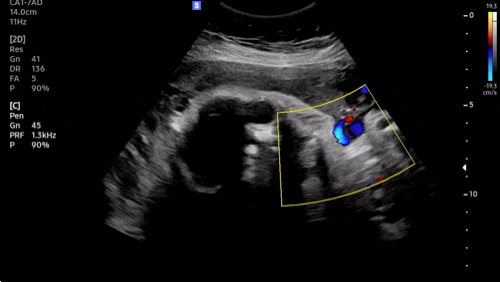

?37주차 증상? 1) 양수검사 늘 넘쳐나던 양수가 줄어들엇다고 하셨다!!! 네?!!!! 안암고대병원에서도...